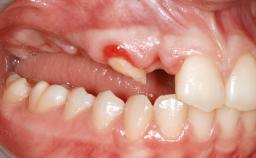

Replacement of Multiple Teeth in a Partially Dentate Posterior Mandible with a Fixed Dental Prosthesis Using a Flapless Approach

Her chief complaint was her inability to masticate efficiently due to the recent loss of her mandibular second premolars and first molars bilaterally. She expressed a desire for fixed prostheses in the shortest possible time due to her advanced age, requesting that replacement teeth should look as natural as possible. She was otherwise comfortable and not experiencing any symptoms from her teeth.